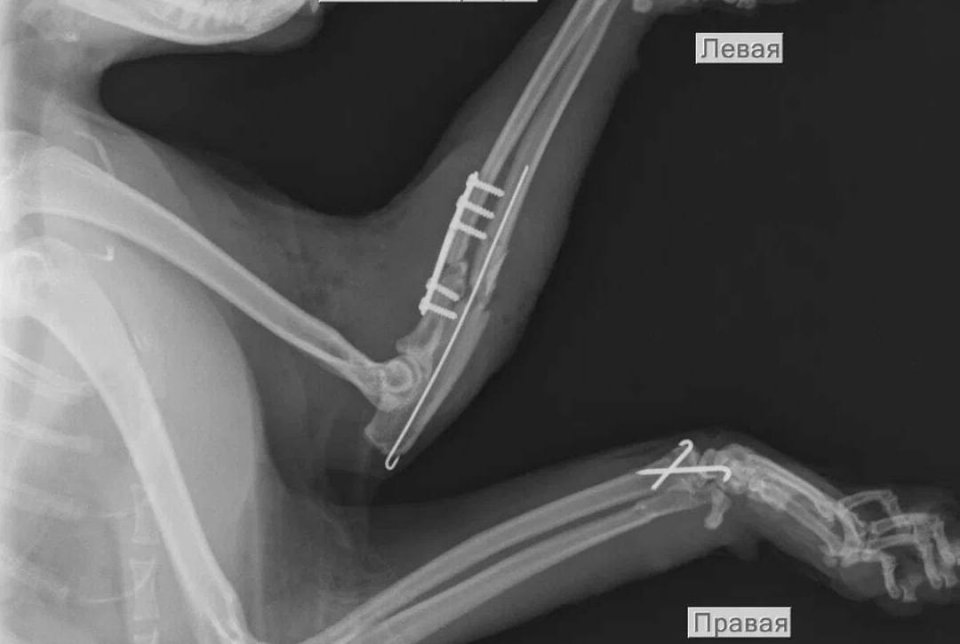

Жителям Печенгского округа на ветстанции стали доступны услуги рентгена для их домашних питомцев. Об этом сообщили в комитете по ветеринарии Мурманской области.

— Жители округа имеют доступ к одной из наиболее информативных и востребованных диагностических процедур в области ветеринарной медицины — рентгенографии, — сообщили в администрации муниципалитета.

Там пояснили, что Печенгская районная ветеринарная станция получила лицензию на использование источников ионизирующего излучения.

Теперь для рентгенографии с заболевшими кошками, собаками и другими домашними животными не нужно выезжать за пределы округа. Её можно сделать в Никеле в ветстанции по адресу: ул. Мира, д. 3б.

Ранее сообщалось, что диагностическое оборудование в рентгенкабинете было установлено в мае этого года, после чего шло документальное оформление и лицензирование объекта.

Фото: Комитет по ветеринарии Мурманской области